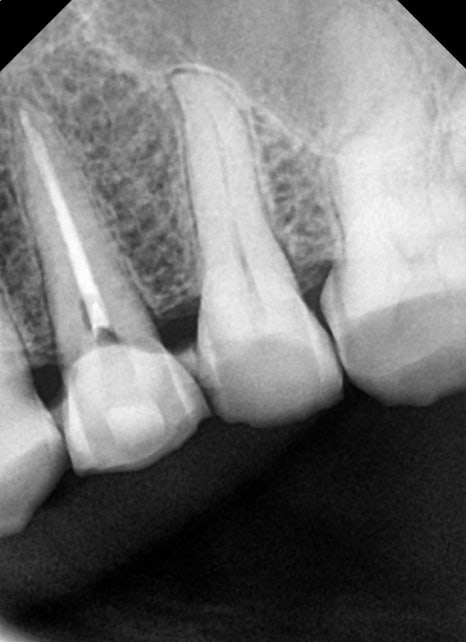

이렇게 x-ray상에서도 크랙으로 인한 파절선은 명확히 보이지 않습니다.